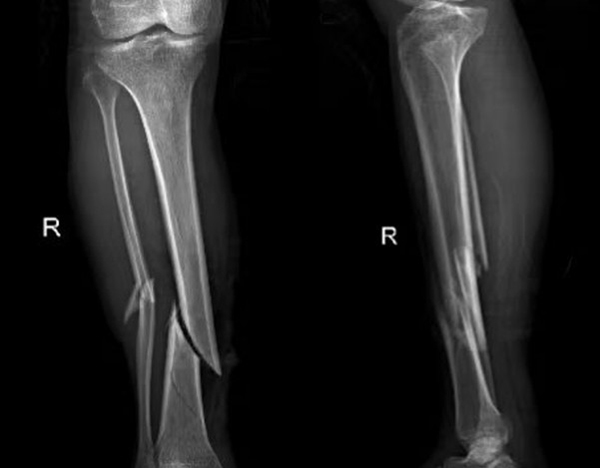

比如外傷患者,排查有無四肢骨折,X光片是首選,因?yàn)樗芸焖偾逦@示骨骼的連續(xù)性;而檢查關(guān)節(jié)內(nèi)的軟組織(如韌帶、半月板),則需要靠MRI,CT對此幾乎“無能為力”。所以,別主動要求“升級”檢查,聽從醫(yī)生的專業(yè)建議,才能既準(zhǔn)確又高效。